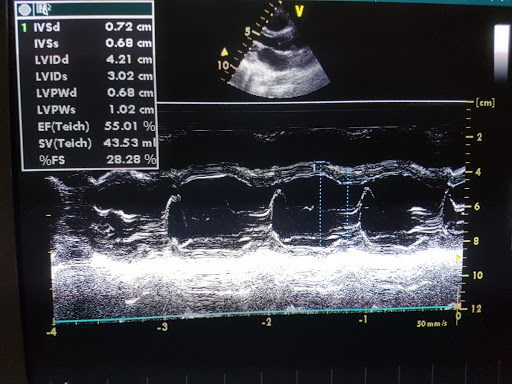

Uzimajući u obzir širok spektar bolesti koje daju isti simptom-zamaranje, neophodno je obaviti internistički i kardiološki pregled radi utvrđivanja uzroka tegoba. Dodatne metode koje nam omogućavaju postavljanje tačne dijagnoze su analize krvi ( vrstu analize indikuje kardiolog nakon obavljenog kliničkog pregleda), ultrazvučni pregled srca, radiografija srca i pluća. Dijagnostički pristup se određuje individualno za svakog pacijenta.